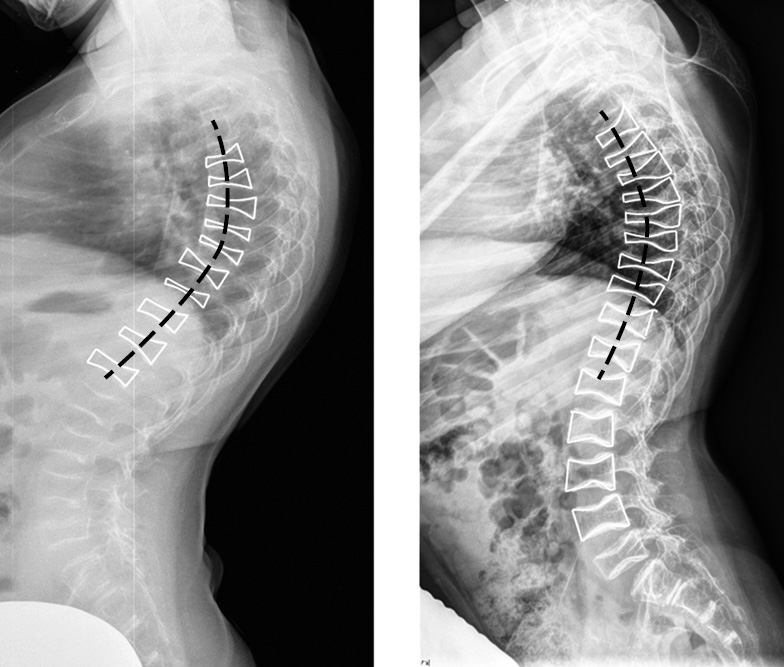

Spinal radiographs of both patients showed increased thoracic kyphosis, decreased height of vertebral bodies (particularly in the central and anterior regions), “fish vertebrae” contours, anisospondylia (varying height of adjacent deformed vertebral bodies), more vertical positioning of ribs (primarily in the upper thorax), and a general decrease in vertebral body BMD (Figs. 2 and 3).

Fig. 2. Lateral projection spine radiographs of patients 1 and 2: increased thoracic kyphosis (black dashed line); decreased vertebral body height, mainly in the central and anterior parts with formation of “fish vertebrae” contours (white lines), most pronounced at the apex of kyphosis; anisospondylia (different heights of adjacent deformed vertebral bodies); overall decrease in bone mineral density of vertebral bodies